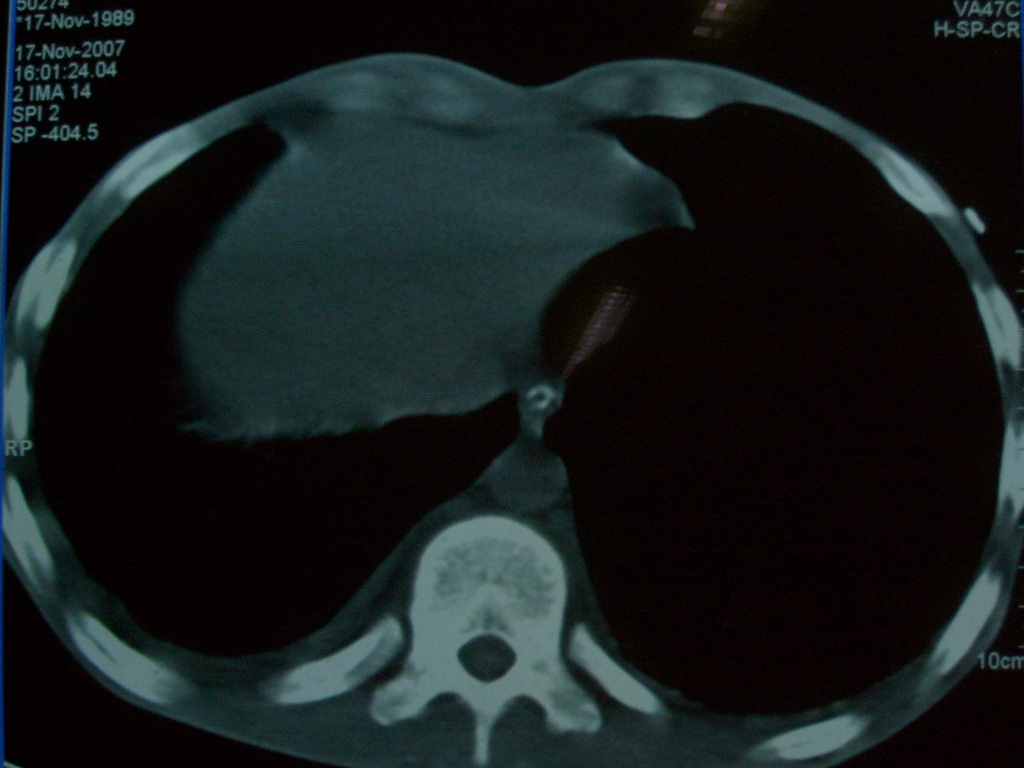

标题: CT10510:男.18岁,咳嗽咳痰两月.(有病理) [打印本页]

标题: CT10510:男.18岁,咳嗽咳痰两月.(有病理)

双肺结核并播散.患者以肠梗阻入院,手术为肠结核.术后咳嗽做ct检查.